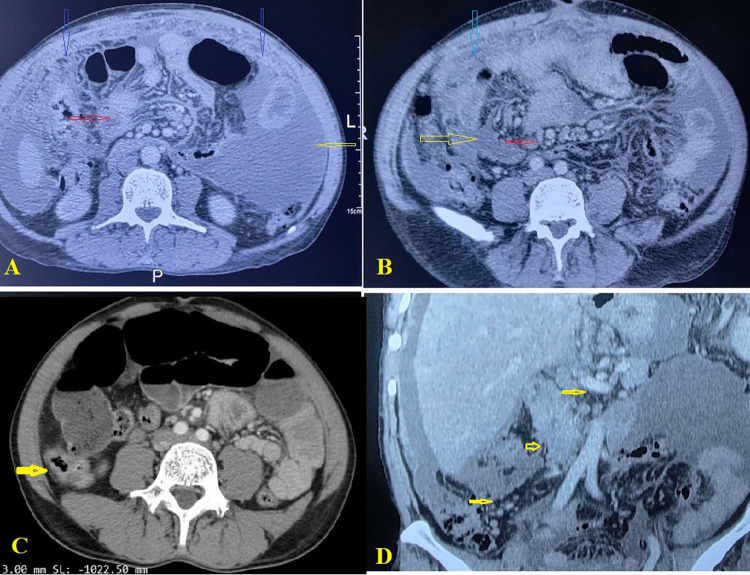

Results: 96 patients with iTB were included, with a mean age of 36.1 ± 11.5 years and a relatively proportionate gender distribution. Abdominal pain was the most common presenting symptom (45.8%). The radiological features varied by the modality. Plain imaging showed non-specific findings, while ultrasonography showed loculated ascites (25%), and lymphadenopathy (22%). In computed tomography scans, multi-segmental symmetric intestinal thickening (53.1%) was the most prevalent finding. The most commonly performed surgical procedure was adhesiolysis (29.2%), with the ileocecal junction being the most commonly involved structure (39.6%). Histopathological examination of all the tissue biopsies revealed epithelioid granulomas. Postoperative complications occurred in 19 patients (19.8%), with surgical site infection being the most common complication (10.4%).